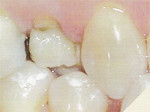

La Carie avancée

Une de vos dents est cariée au point de ne pas pouvoir la reconstruire par des obturations classiques (plombage, composite, inlay). Une couronne s'impose, pourtant, il n'est pas nécessaire de dévitaliser votre dent.

ancienne obturation - Ancienne obturation

Une dent déjà obturée sur deux ou trois faces présente une nouvelle carie sous ou à côté de cette obturation. Mais la matière profonde subsiste.

- Fracture

Une dent reconstituée par une opturation volumineuse : celle-ci a fracturé la dent et provoqué la perte d'une grande partie de la couronne.